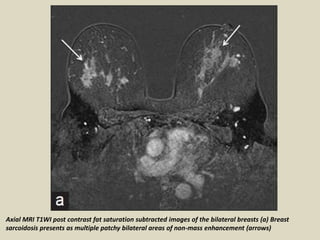

Axial MRI T1WI post contrast fat saturation subtracted images of the bilateral breasts (a) Breast

sarcoidosis presents as multiple patchy bilateral areas of non-mass enhancement (arrows)